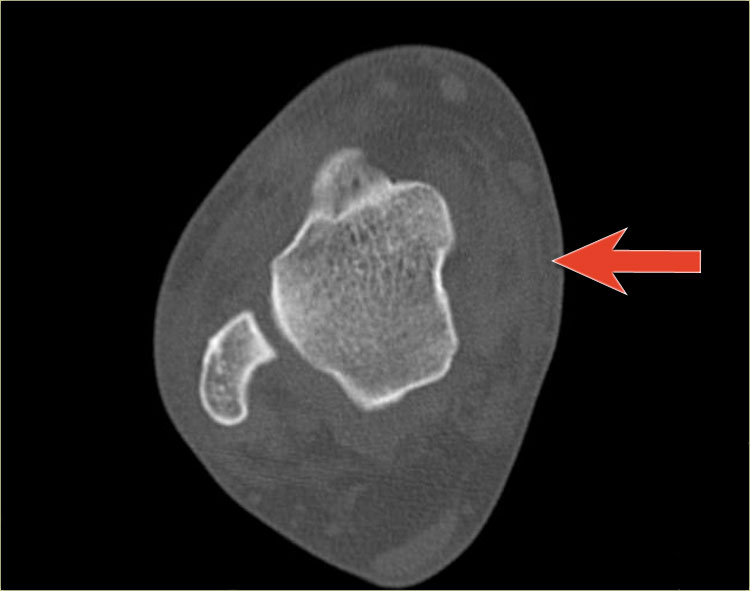

Hãy quan sát các hình ảnh và sau đó cuộn sang hình ảnh tiếp theo.

Đường gãy qua đầu xương có thể dễ bị bỏ sót (mũi tên xanh).

Đường gãy qua tấm sụn tiếp hợp chỉ được phát hiện trên CT.

Tiếp tục xem các hình ảnh CT.

Các hình ảnh CT thể hiện rõ ràng đường gãy qua tấm sụn tiếp hợp và đầu xương.